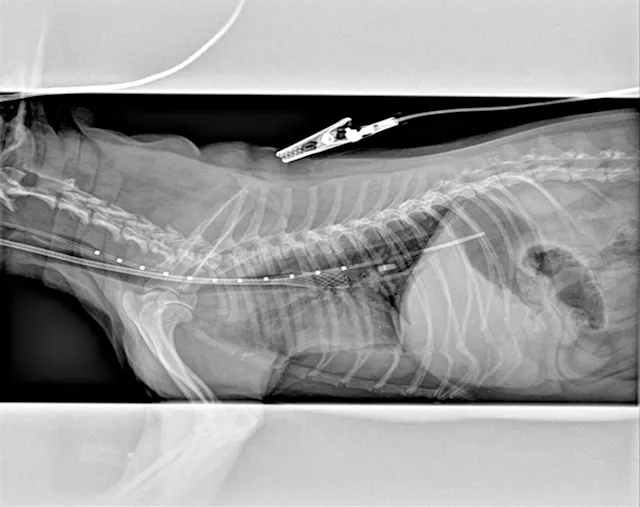

Definitive diagnosis is based on imaging (eg, survey radiography, fluoroscopy, ultrasonography, computed tomography, tracheobronchoscopy).13 Survey radiography should include dorsoventral and lateral views of the cervical region and thorax (Figure 1). Collapse of the trachea is best viewed in the cervical region during inspiration and in the intrathoracic region during exhalation.1 Radiography is critical to rule out conditions that may cause similar signs (eg, intrathoracic masses, pleural effusion) and cardiovascular abnormalities (eg, heart enlargement) that may complicate treatment. Radiography is noninvasive, cost effective, widely available, and can be performed without the risks associated with general anesthesia; however, false-positive results have been reported in 25% of dogs,14 and sensitivity ranges from 60% to 90%.2 In comparison, fluoroscopy allows direct viewing of tracheal motion during all phases of respiration, is noninvasive, and is very sensitive, although false-positive findings have also been reported with fluoroscopy.14 In one study, radiography underestimated the severity and frequency of collapse as compared with fluoroscopy.15

Lateral thoracic radiograph of a dog with tracheal collapse. The most severe area of collapse is just caudal to the thoracic inlet.